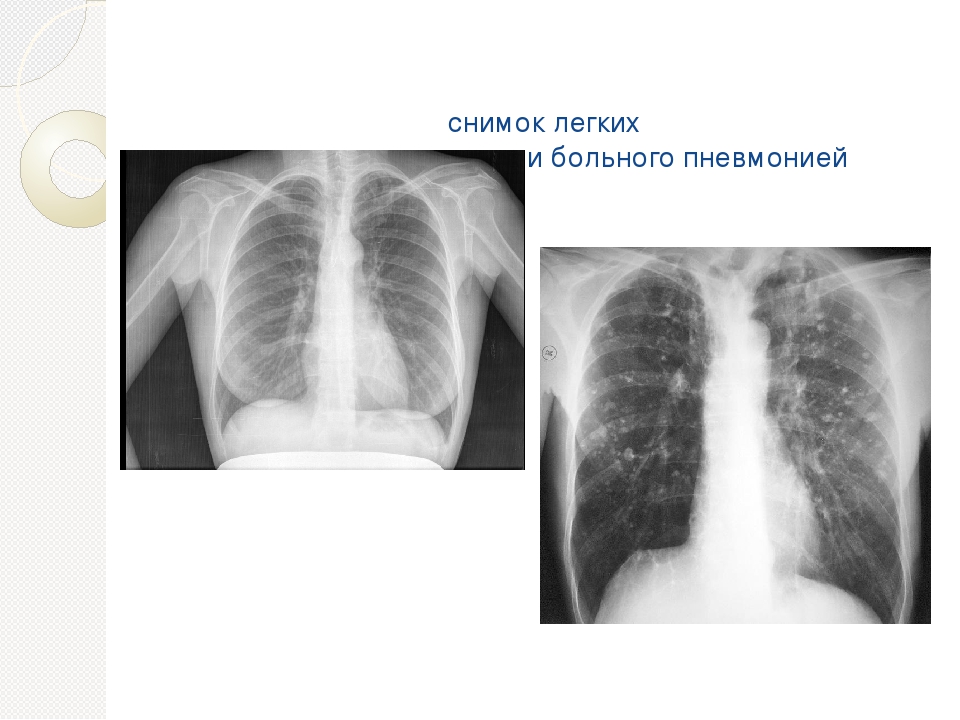

Снимок грудной клетки здорового ребенка: примеры и диагностика